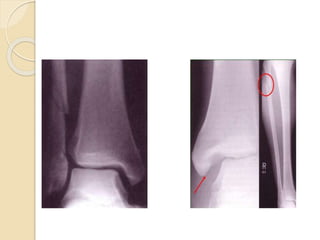

 La exploración radiográfica habitual del

tobillo incluye proyecciones anteroposterior,

lateral y de la mortaja; esta última se hace

en sentido anteroposterior pero con 20

grados de rotación interna.

 En ocasiones será necesario recurrir a

otros estudios de imagen donde la

tomografía 3D es el de elección, sobre

todo para valorar, lesiones

osteocartilaginosas.